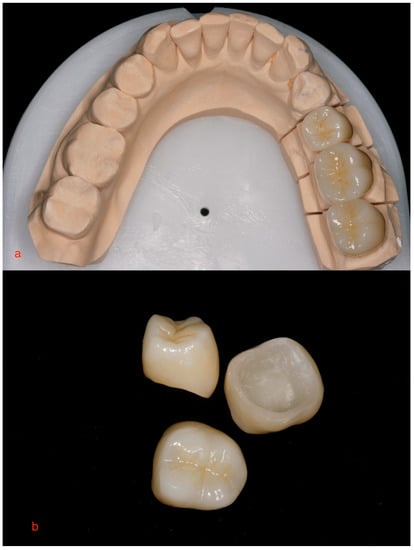

2. Materials and Methods